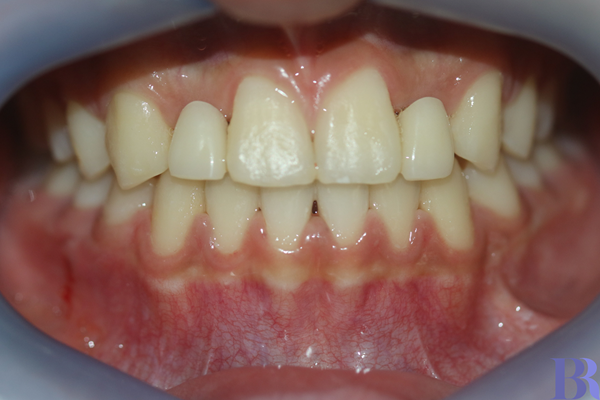

교정 후 정면 모습

반대교합이 해결되었으며,

위에 앞니 두 개의 공간도

충분히 확보해주었습니다.

아직 나이가 어려서

임플란트를 할 수 없어서

가공치를 배치하였습니다.

* 임플란트는 성장 완료 후 식립